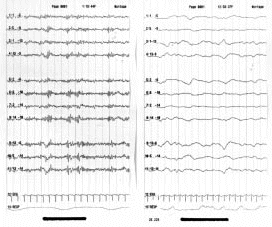

Figura 8.- Dos tipos de trazados electroencefalográficos de pacientes en coma. En el de la izquierda la actividad es de tipo rápido y en el de la derecha de tipo lento.